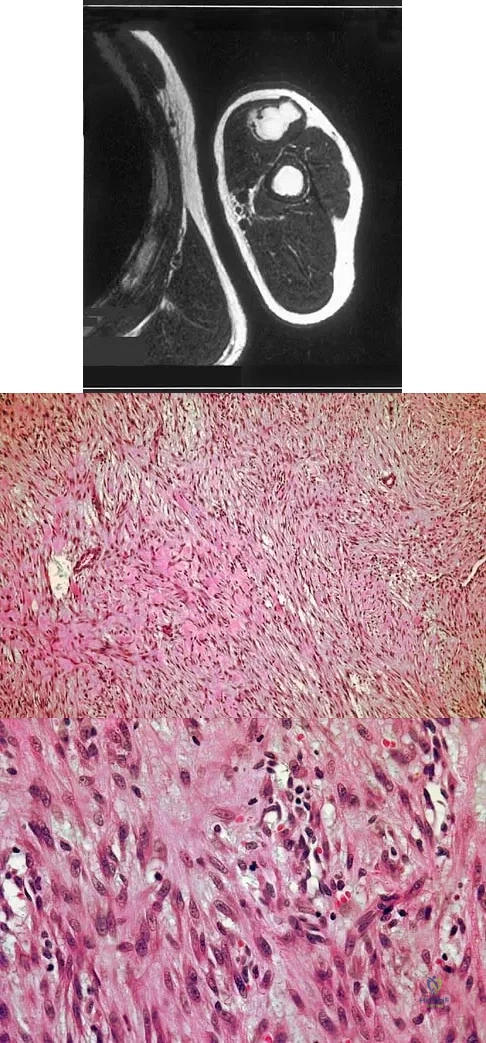

A 14-year-old boy has an asymptomatic mass on the right arm. MRI scans and biopsy specimens are shown in Figures 51a through 51d. Immunostaining is positive for desmin. Additional staging studies should include